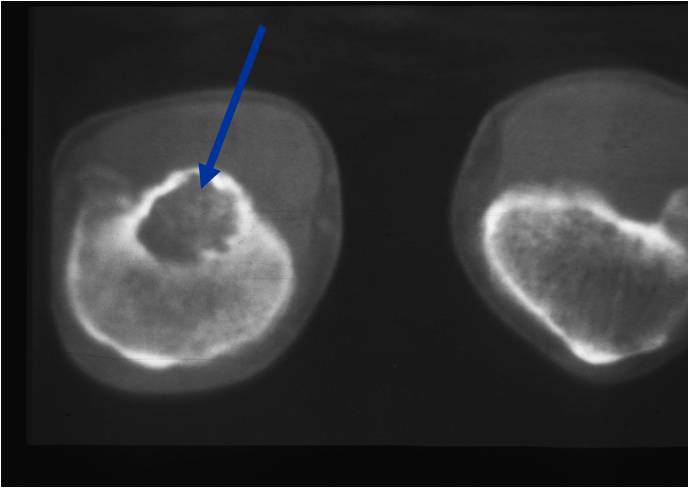

- (CT appearance)

- Most useful for detecting subtle mineralization not apparent on X-rays

- Useful for identifying intact periosteum around any expansile soft tissue component

- surrounding thin reactive shell of bone/mineralization (Egg Shell Rim of Calcification)

- helps place the tumor in a benign category

- helps evaluate:

- bony quality

- extent of bone and cortical destruction

- whether the subchondral plate of bone adjacent to the articular cartilage has been destroyed or is intact